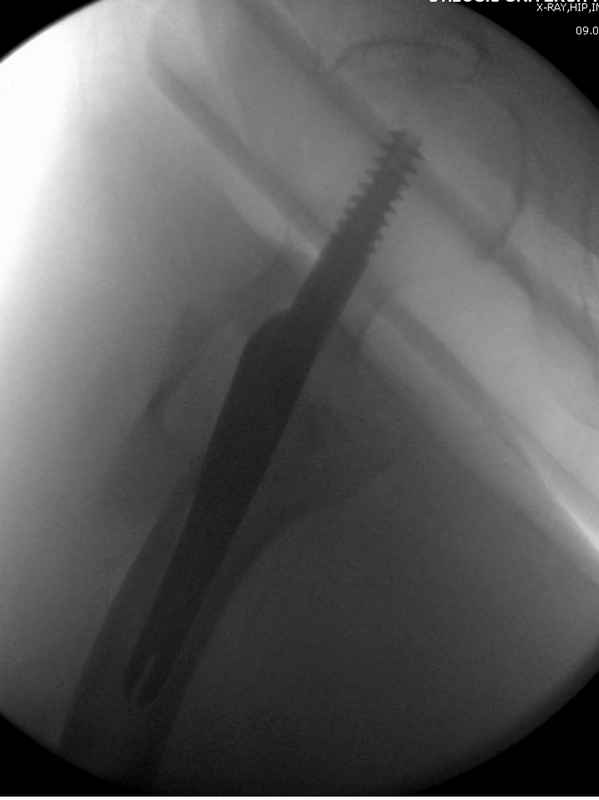

Здесь 83 года, травма в результате падения

Из фиксаторов, мы бы применили цефаломедуллярные, потому что они "по закону моментов" из-за короткого рычага от центра головки к диафизу и по принципу "головка диафиз" механически лучше выдерживают нагрузки, чем пластины.

Но современные пластины с угловой стабильностью не отстают от медуллярных конструкций. Межфрагментарные шурупы и имплант как нейтрализирующее создаст адекватную фиксацию.

судя по картинкам с ЭОПа явно использовались приемы непрямой репозиции под его контролем, а так же интраоперационный ЭОП-контроль положения винтов, без такого контроля операция может ухудшить ситуацию (опять же учтите сроки) т.к. результат буде зависеть в большей степени от искусства хирурга, а не от технологии